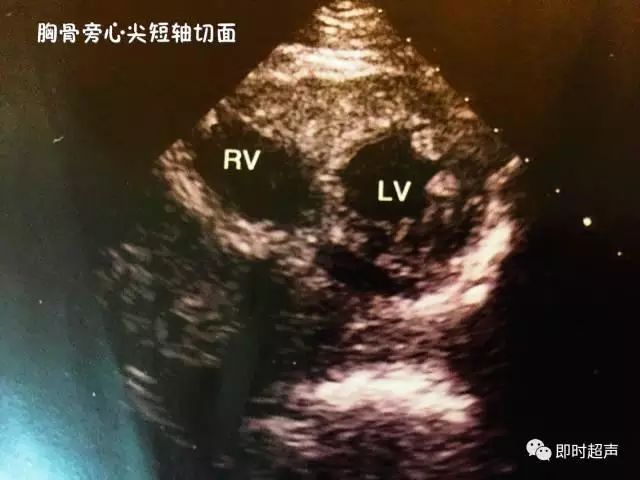

六、胸骨旁心尖短轴切面

主要观察:左心室近心尖的病变,如心尖室壁瘤、血栓等。